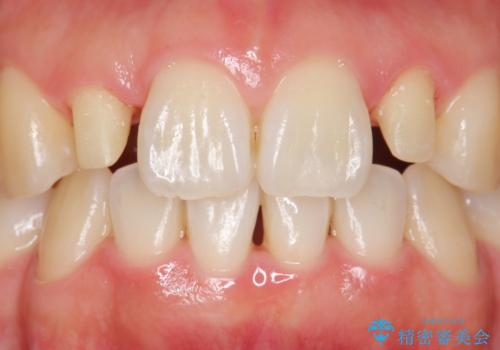

- 口元を綺麗にしたいとのご希望により来院された患者様です。

全顎的に歯並びにがたつきがあり、上の側切歯(上顎両側2)は生まれつき小さい歯(矮小歯)でした。

矯正治療後、矮小歯をセラミッククラウンにより理想的な歯の大きさに仕上げました。

※矯正治療は井上副院長が行っております。